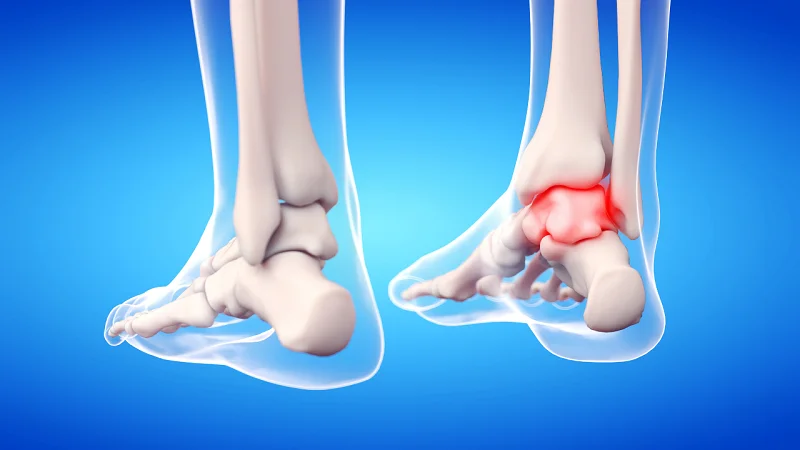

1. Joint Replacement Surgery (Knee, Hip)

The procedure involves replacing damaged knee or hip joints with artificial implants through advanced surgical methods which doctors recommend for patients with severe arthritis who experience unbearable pain. Modern implants used in procedures like knee replacement surgery enable patients to achieve complete pain relief and restored mobility with a 6-12 weeks recovery period.